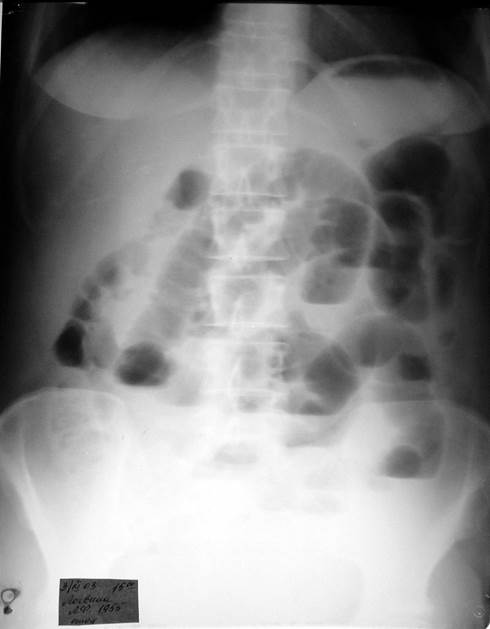

Вопросы к рис. 2:

1) Назовите рентгенологический метод исследования пациента, представленный на иллюстрации.

2) Назовите ведущий рентгенологический признак острой кишечной непроходимости и покажите его на рентгенограмме.

Рис. 2

Ответы:

1) Обзорная рентгенография брюшной полости.

2) На рентгенограмме определяются «чаши Клойбера» – вздутие петель кишечника с наличием скопления жидкости, образующей горизонтальные уровни.